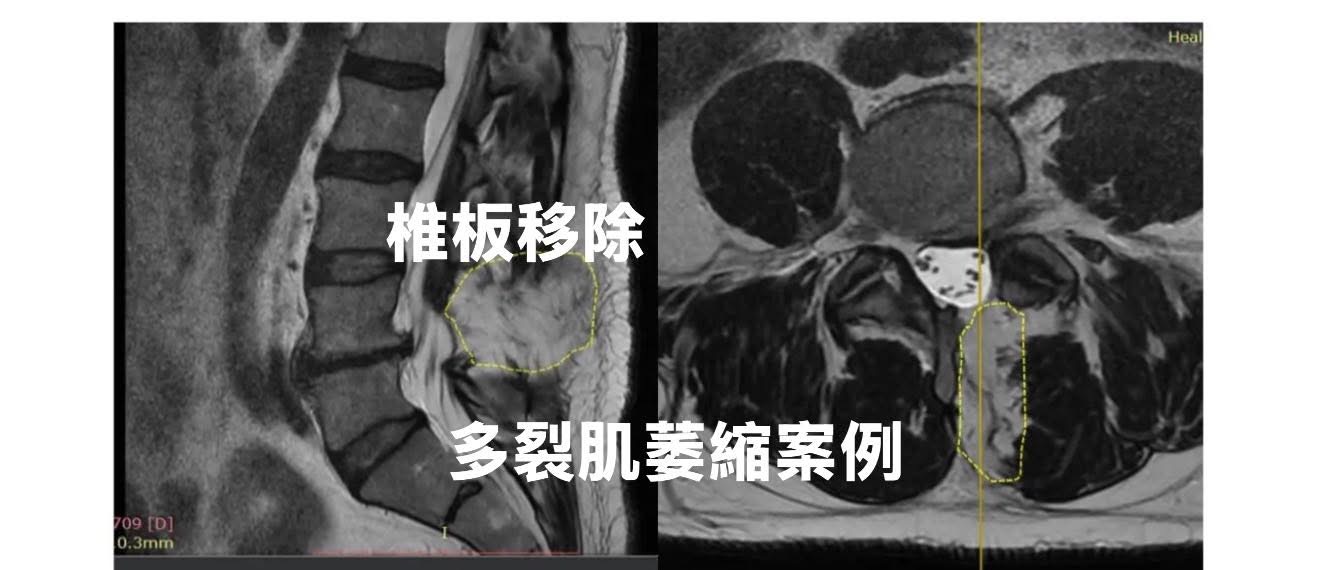

影像內容二

• 左圖(矢狀位 MRI):黃虛線圈出的區域是 L4–L5 寬椎板切除(wide laminectomy)後留下的「空缺」位置,原本應該有部分穩定肌肉(如多裂肌)與韌帶,但因手術切除而變成白色的信號空間(多為纖維化或脂肪化取代)。

• 右圖(軸位 MRI):黃虛線圈出同一個區域,原本深色的肌肉組織在這裡變成白色空洞,表示該處肌肉被切除或萎縮,可能被脂肪或疤痕替代。

臨床重點

• 這不是在描述硬膜外纖維化(epidural fibrosis),而是後柱穩定肌群(multifidus 等)的手術後損傷。

• 多裂肌是脊柱非常重要的穩定肌,負責細微姿勢控制與減少小關節負荷。

• 手術範圍大、切除範圍廣(例如 wide laminectomy),可能導致該區域的穩定肌部分切除、失神經支配,進而出現脂肪浸潤與功能下降。

• 這種變化會讓患者在骨性結構已經「穩定」的情況下,仍有腰部疲勞感、無力感或慢性疼痛。